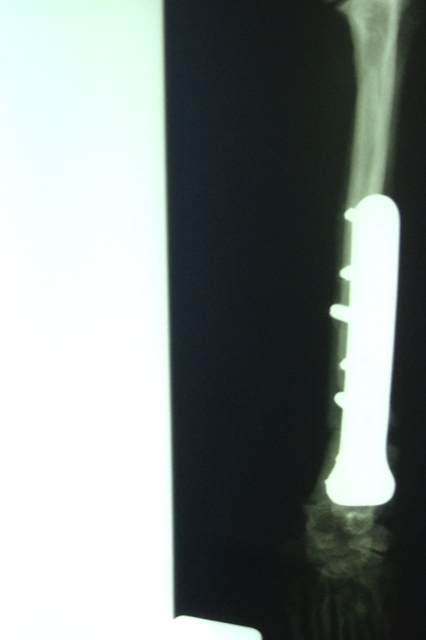

Wir danken herzlich für die Geldspenden, die dies alles erst ermöglicht haben - aber bitten auch dringend um weitere Überweisungen, denn wir mussten heute auch Griffin operieren lassen, der sich mit Kniescheibenproblemen herumplagte. Und weil Lucy auch Probleme zu haben scheint, haben wir sie heute mitgenommen zum Röntgen. Es stellte sich leider heraus, dass sie einen Kreuzbandriss hat, der ebenfalls operiert werden muss.